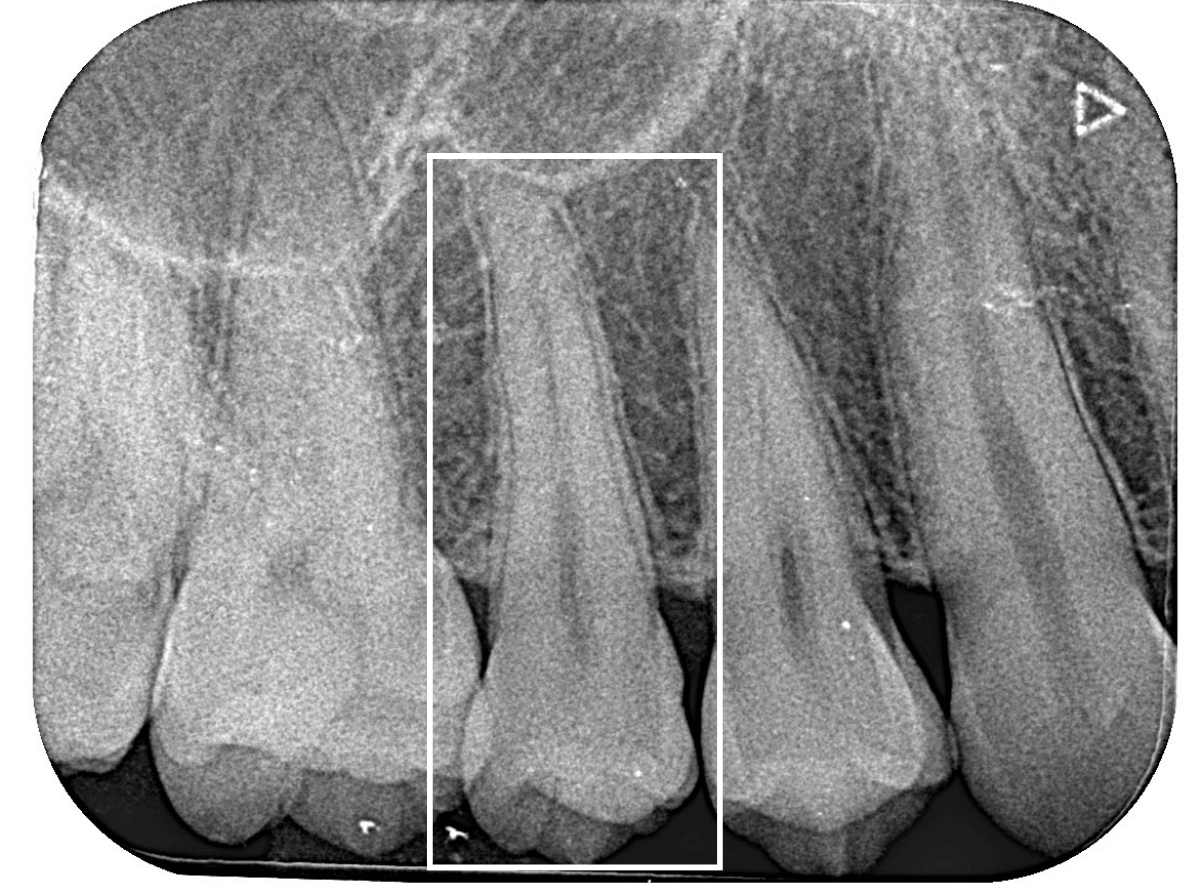

Case.8 大きな虫歯なのに、レントゲンではっきり写らない

こちらも定期検診希望で来院された患者さんです。

お口の中を拝見すると、明らかに虫歯がありました。

3本虫歯になっており、特に中央の小臼歯はかなり大きな虫歯になっているのが予想されます。

治療前にレントゲン写真で虫歯の大きさを確認するつもりが・・・あまりはっきり写ってきません。

患者さんに状況を説明して、歯を少しずつ削りながら虫歯を確認する事になりました。

このように明らかに大きな虫歯があると診断されるような状況でも、レントゲン写真でうまく診断できない場合もあります。